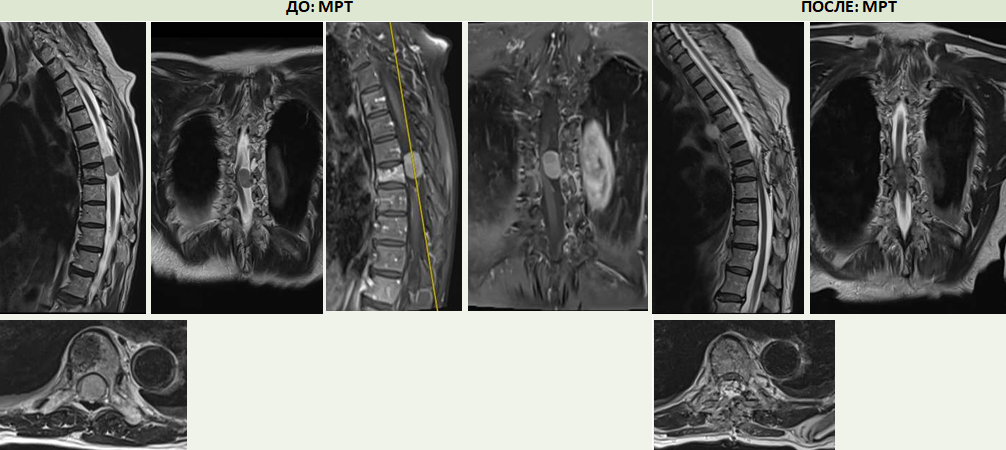

У 76-летней пациентки опухоль росла незаметно до того момента, пока не спровоцировала тяжелые неврологические последствия на фоне поражения спинного мозга. Из-за опухоли в грудном отделе позвоночника у нее полностью пропала чувствительность в левой конечности, возникло нарушение функции тазовых органов, развитие паралича.

Операцию проводили два нейрохирурга Клиники патологии позвоночника и редких заболеваний Алексей Евсюков и Сергей Алексеев. Хирургическое вмешательство под контролем электронного микроскопа длилось несколько часов и было сопряжено с огромным риском для жизни пациентки. Опухоль была радикально удалена, без ущерба позвонкам.

- Во благо сработало много факторов: и оперативность помощи, и правильность выбранной тактики лечения, и технические ресурсы нашего центра – тот же ультразвуковой деструктор, с помощью которого мы аккуратно смогли обойти спинной мозг, ликвидировать это образование и достать его целиком. Объем опухоли порядка 2-2,5 сантиметров, канал был перекрыт полностью, компрессия спинного мозга феноменальная, шанс регресса неврологической симптоматики был минимальный, но дальнейший результат нас просто привел в восторг, такого не ожидалось, - поделился Сергей Алексеев, врач-нейрохирург отделения №15 Центра Илизарова.

Буквально на следующий день чувствительность в левой ноге вернулась. После курса реабилитации с инструктором-методистом ЛФК отделения ранней медицинской реабилитации Андреем Григорьевым пациентка начала подниматься и ходить с помощью средств опоры.